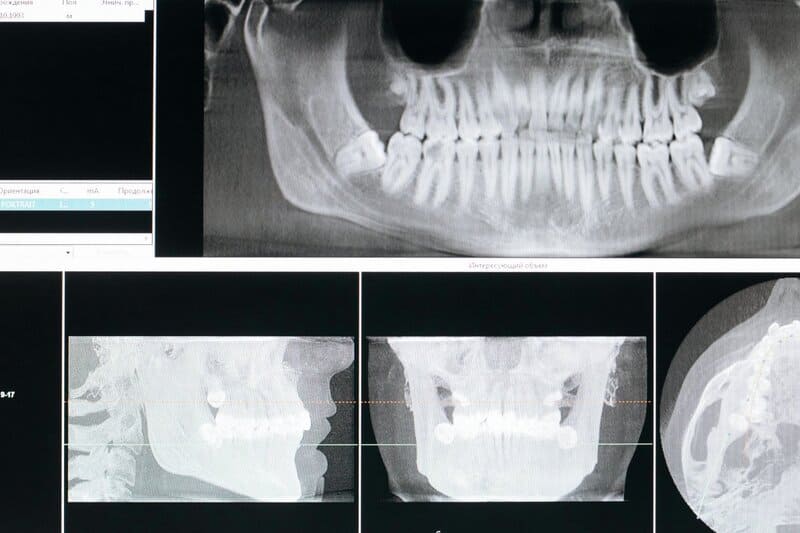

Most people understand that poor dental hygiene leads to cavities and gum disease, but groundbreaking research reveals a far more serious consequence: it could be silently threatening your heart. A remarkable 17-year study following older adults found that those with periodontitis faced a 50% higher risk of developing ischemic heart disease, with women showing an even more alarming 110% increased risk. Even more striking, recent research shows that seniors with no remaining teeth have an 83% higher risk of dying from cardiovascular disease compared to those who’ve maintained at least 20 teeth. This isn’t just about statistics—it’s about a hidden health crisis affecting millions of older adults. As we age, the stakes of dental neglect become literally a matter of life and death. The mouth, once thought to be separate from the rest of the body, is now recognized as a gateway that can either protect or endanger our cardiovascular system.